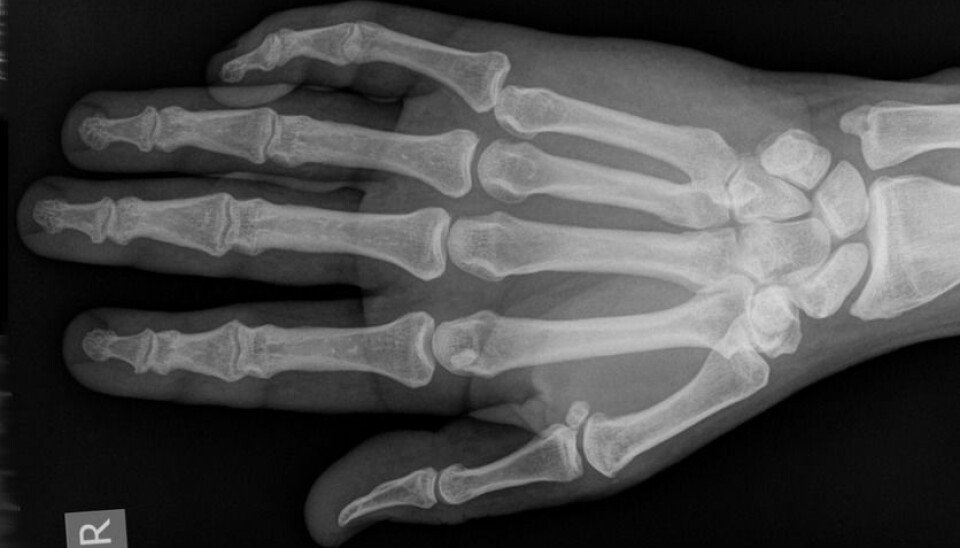

Forskere har MR-filmet hvordan knekkelyden oppstår når du tøyer og bøyer på fingrene dine. (Foto: Hellerhoff, Wikimedia Commons. Lisens: Creative Commons Navngivelse-DelPåSammeVilkår 3.0 Unported)

Fryer ble plassert i MRI-skanneren mens han knakk fingrene sine. Det er hans fingre du ser på videoen.